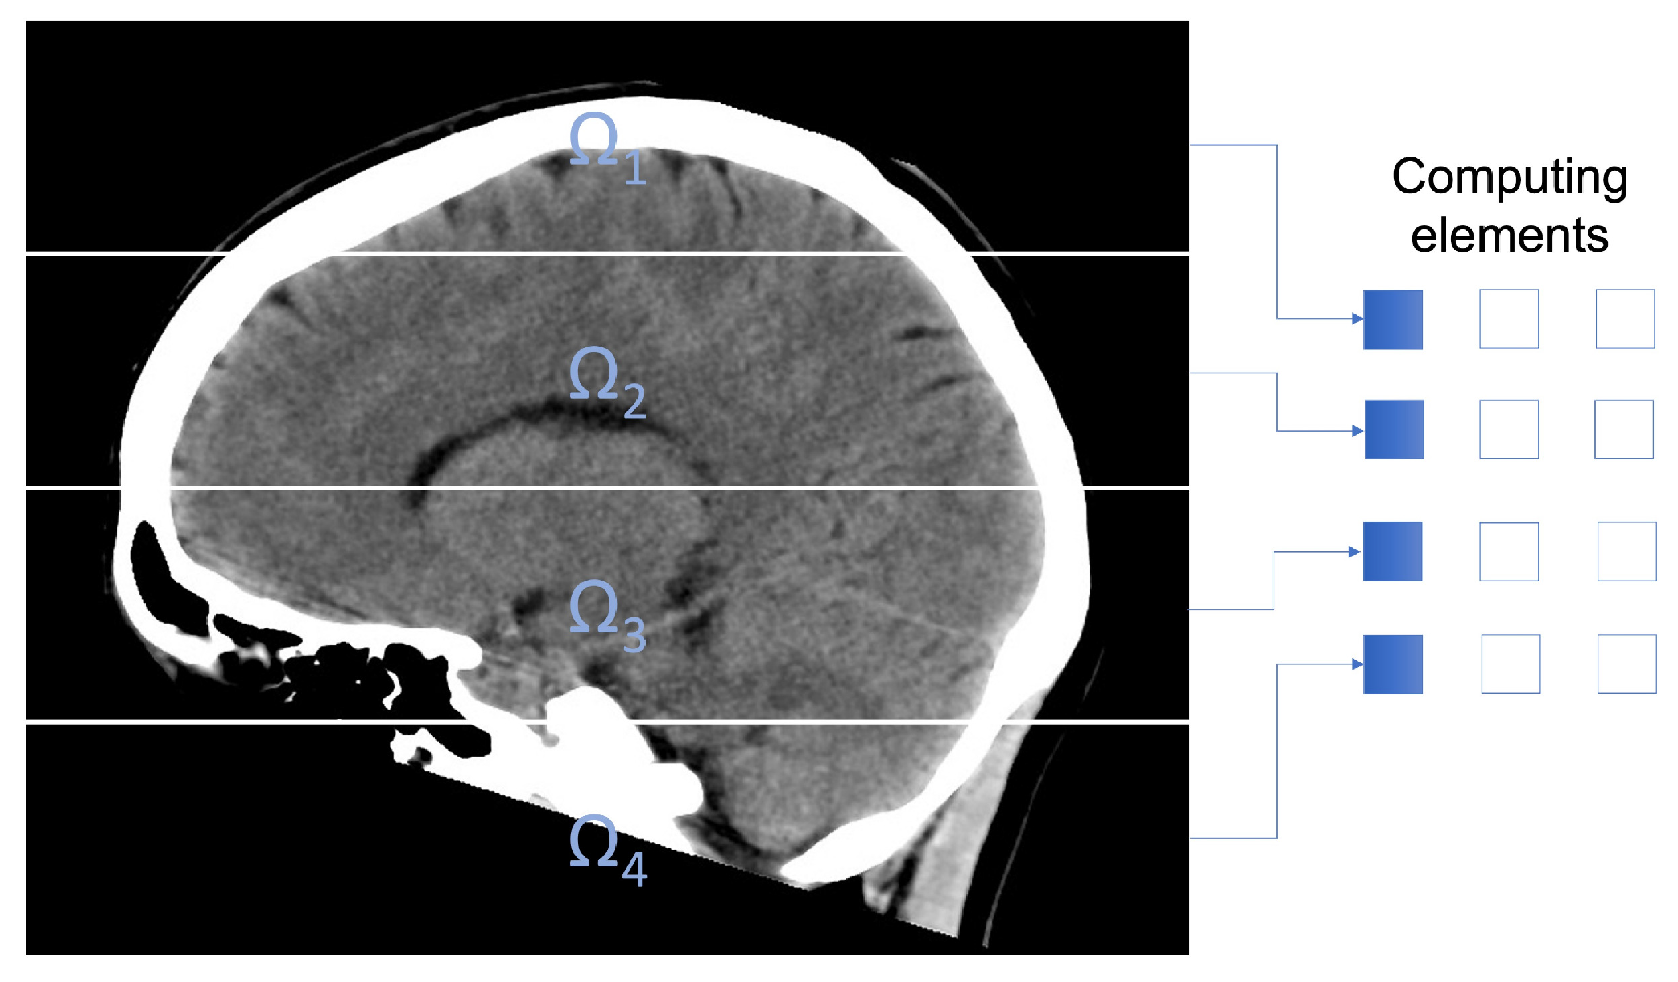

2.3. Parallel Fuzzy Filter

To reduce the computing times, a parallel method based on the described algorithm is introduced. In order to distribute the pixels of the medical image among the computing units in the parallel computer, the domain Ω of the image is split in P subdomains Ω i , i = 1 , P , being P the amount of computing units. This decomposition fulfills

Figure 1 exemplifies the subdomains utilized in the experimentation.

Figure 1. CT image decomposition using 4 subdomains.

To filter pixels located in the internal frontier of the subdomains, every computation unit requires of some extra pixels. Therefore, we establish an overlapping domain decomposition. Figure 2 shows an overlapping domain decomposition using four subdomains. To describe the overlap, we consider Ω i λ , i = 1 , , P ; an expansion of Ω i , being λ a natural number defining the proportions of the overlapping area. Computation unit k filters pixels in subdomain Ω k , but utilizing pixels in subdomain Ω k λ . λ is the integer part of the number n / 2 , being n × n the dimensions of the processing window.

Figure 2. Overlapping domain decomposition using four subdomains.